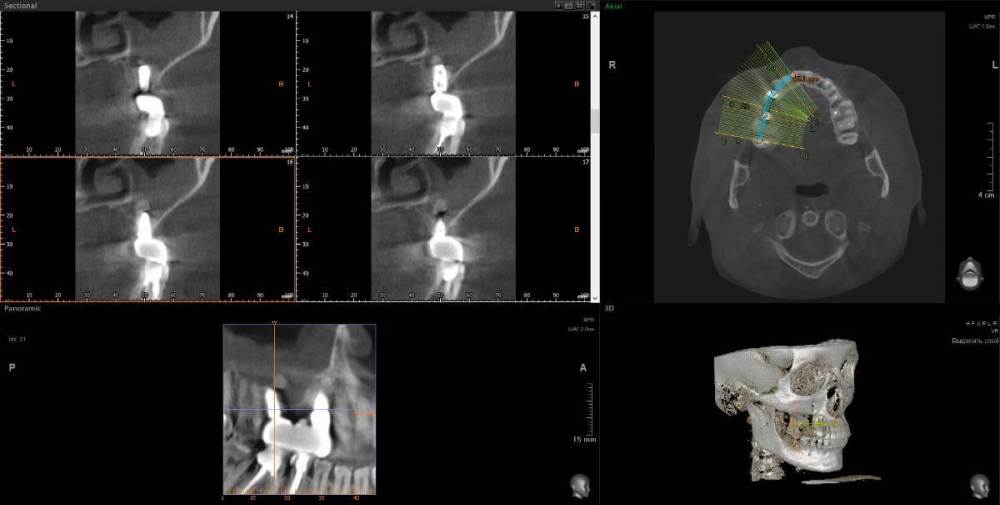

1. Сильное воспаление верхнего зуба привело к воспалению пазухи носа 2. Импланты 2 года (общая ст-ть 200 тыс.), тоже воспаление, рекомендовано удалить

1. Из-за сильного воспаления верхнего зуба костная кость растворилась и дошло до пазух носа. Зуб рекомендуют удалить

2. Импланты установила 2 года назад, в итоге заплачено было 200 тыс. с учетом циркониевых коронок. На КТ обнаружилось сильное воспаление, как следствие растворилась костная ткань импланты, доктор сказал уже не спасти.

Буду очень признательна за консультацию - действительно ли нужно удалять зуб и импланты? КТ во вложении

IMHO. Зуб 18 стоит удалить, зуб 17 стоит полечить. Имплантат в позиции 16, похоже, придётся удалить, имплантат в позиции 14, на мой взгляд, вне опасности.